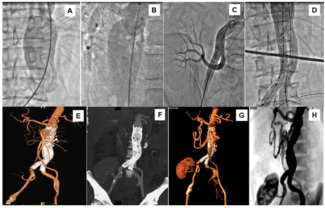

A 45-year-old man presented with pain in the abdomen and pulsatile abdominal swelling of 3-month duration. He had kidney transplantation for chronic kidney disease 2 years prior. Computed tomography (CT) angiography revealed a 10.0-cm x...